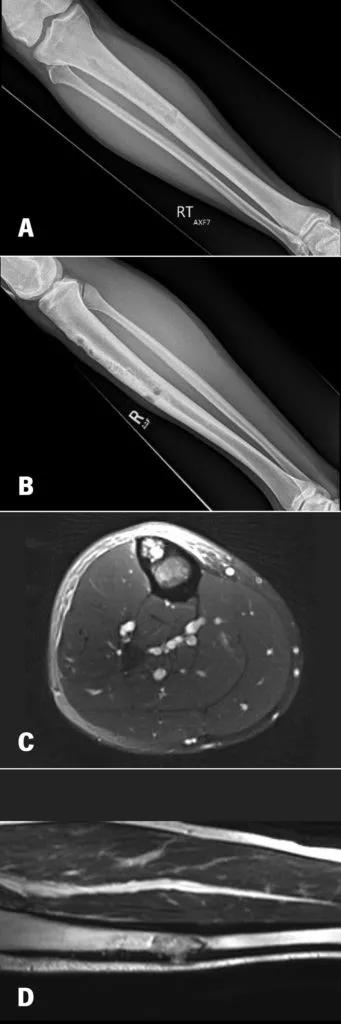

A 23-year-old former marine presented with one year of tibial pain that progressed to a point where he quit running. Imaging (Figure 1) suggested a diaphyseal tibial lesion. A core needle biopsy of the large lytic lesion (red arrow) suggested a classic type of adamantinoma. Systemic staging studies showed localized disease only.

Figure 1. 28-year-old with 12 months of tibial pain. AP and Lateral Radiographs (A, B) show a cortically based anterior tibial lesion, with axial (C) and coronal (D) MRI imaging suggesting cortical breakthrough and an aggressive marrow replacing process.